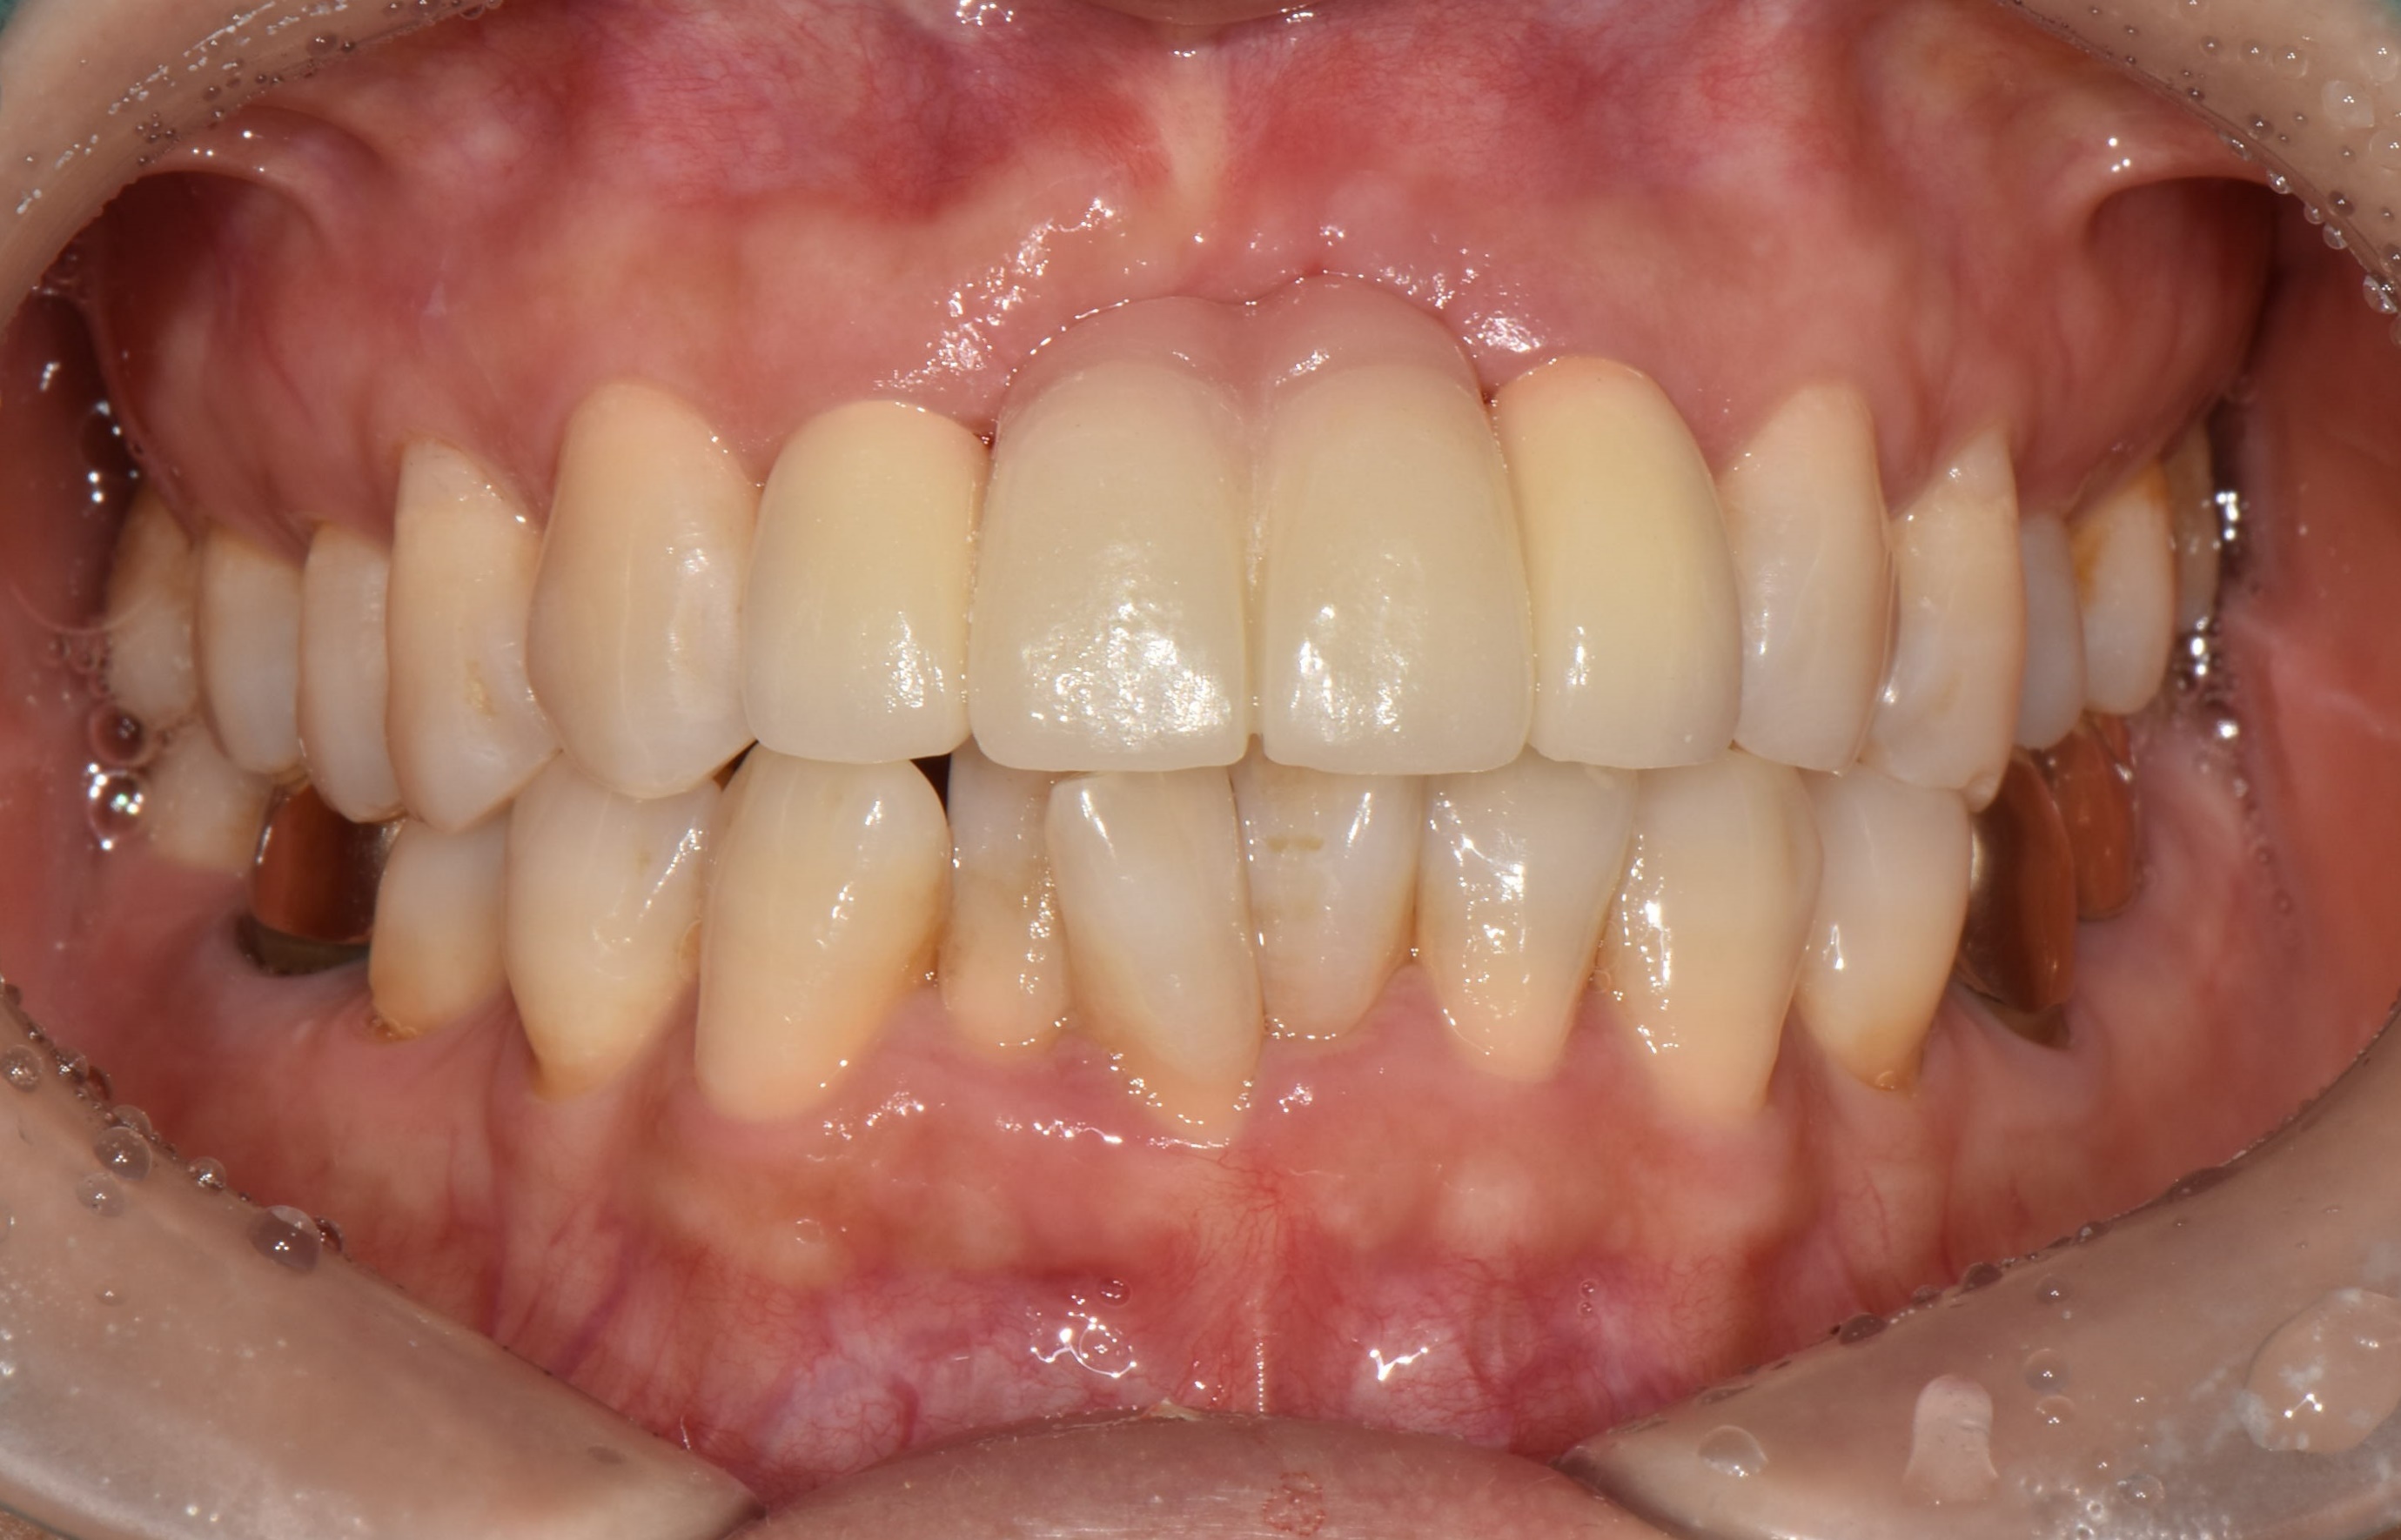

수술 전

수술 후

치근단 절제술 사례

전후사진